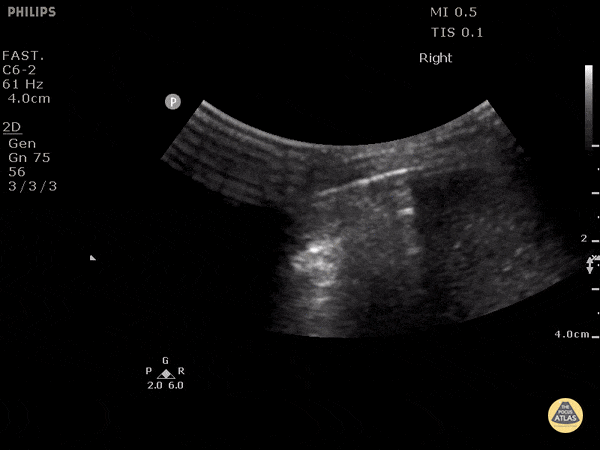

8 year old boy after pushbike handles went into abdomen. Erect CXR suggested small pneumoperitoneum. This image shows a lung curtain across the liver. Dr. Justin Bowra